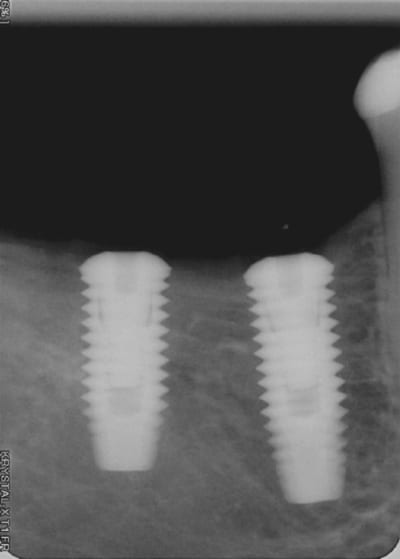

Je voulais vous faire découvrir un petit outil que j'ai inventé et fait fabriqué pour m'aider dans le positionnement d'un ou plusieurs implants , au cours de la chirurgie.

C'est sur que c'est a des années lumières des guides ultra sophistiqués de chirurgie guidée, mais je peux vous assurer que je m'en sert tous les jours et pour un moindre cout.

en PJ vous trouverez une photo de la bête ainsi qu'un article explicatif.

je viens de faire ma première pose avec "the" outil (merci clio pour la livraison ultra-rapide:)

remplacement de 46 et 47

Petite bouche mais ouverture pas trop limitée. Pour 46, point de forage à 5 mm de la 45 (3 ème cran contre la 5 et forage au milieu de la gorge centrale) puis pour la 47 j'ai choisi de forer à 8 mm du point de 46 en raison de l'antagoniste (je vais faire une "petite" 47)

mes impressions: très très pratique (çà fait même un peu écarte-joue)